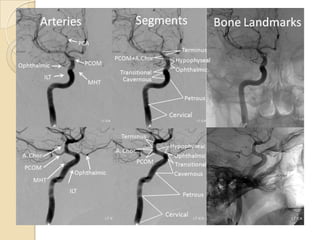

Arteries of the brain (cranial view) - MRA

1. Anterior cerebral artery

2. Anterior communicating artery

3. Basilar artery

4. branches (in insula) of middle

cerebral artery

5. Cavernous portion of internal

carotid artery

6. Cervical portion of internal carotid

artery

7. Genu of middle cerebral artery

8. Intracranial (supraclinoid) internal

9. Middle cerebral artery

10. Ophthalmic artery

11. Petrous portion of internal carotid

12. Posterior cerebral artery

13. Posterior cerebral artery in ambient

cistern

14. posterior cerebral artery in

interpeduncular cistern

15. Posterior communicating artery

16. Posterior inf cerebellar artery.

17. Quadrigeminal portion of posterior

18. Superior cerebellar artery

19. Vertebral artery